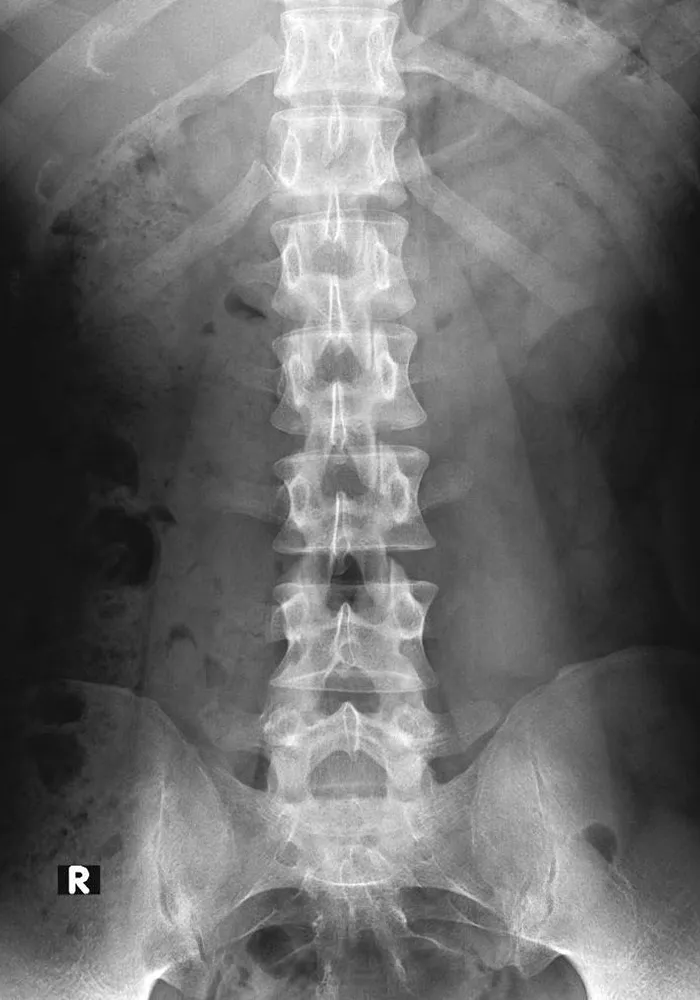

一般撮影

一般撮影は診断目的とする部分にX線を照射して撮影を行う検査です。X線は体内を通過する際に骨や筋肉、内臓などの組織により吸収される量が変化するので、透過したX線量の差を画像化したものがレントゲン写真となります。

当院の一般撮影室は 2室 あり、いずれも フラットパネルディテクタ(FPD)対応 の最新機器を導入しています。FPDを用いることで、従来よりも少ないX線量で効率的に撮影でき、より高画質な画像を得ることが可能です。これにより、患者様の被ばく線量をできる限り低減しつつ、迅速で正確な診断に役立てています。